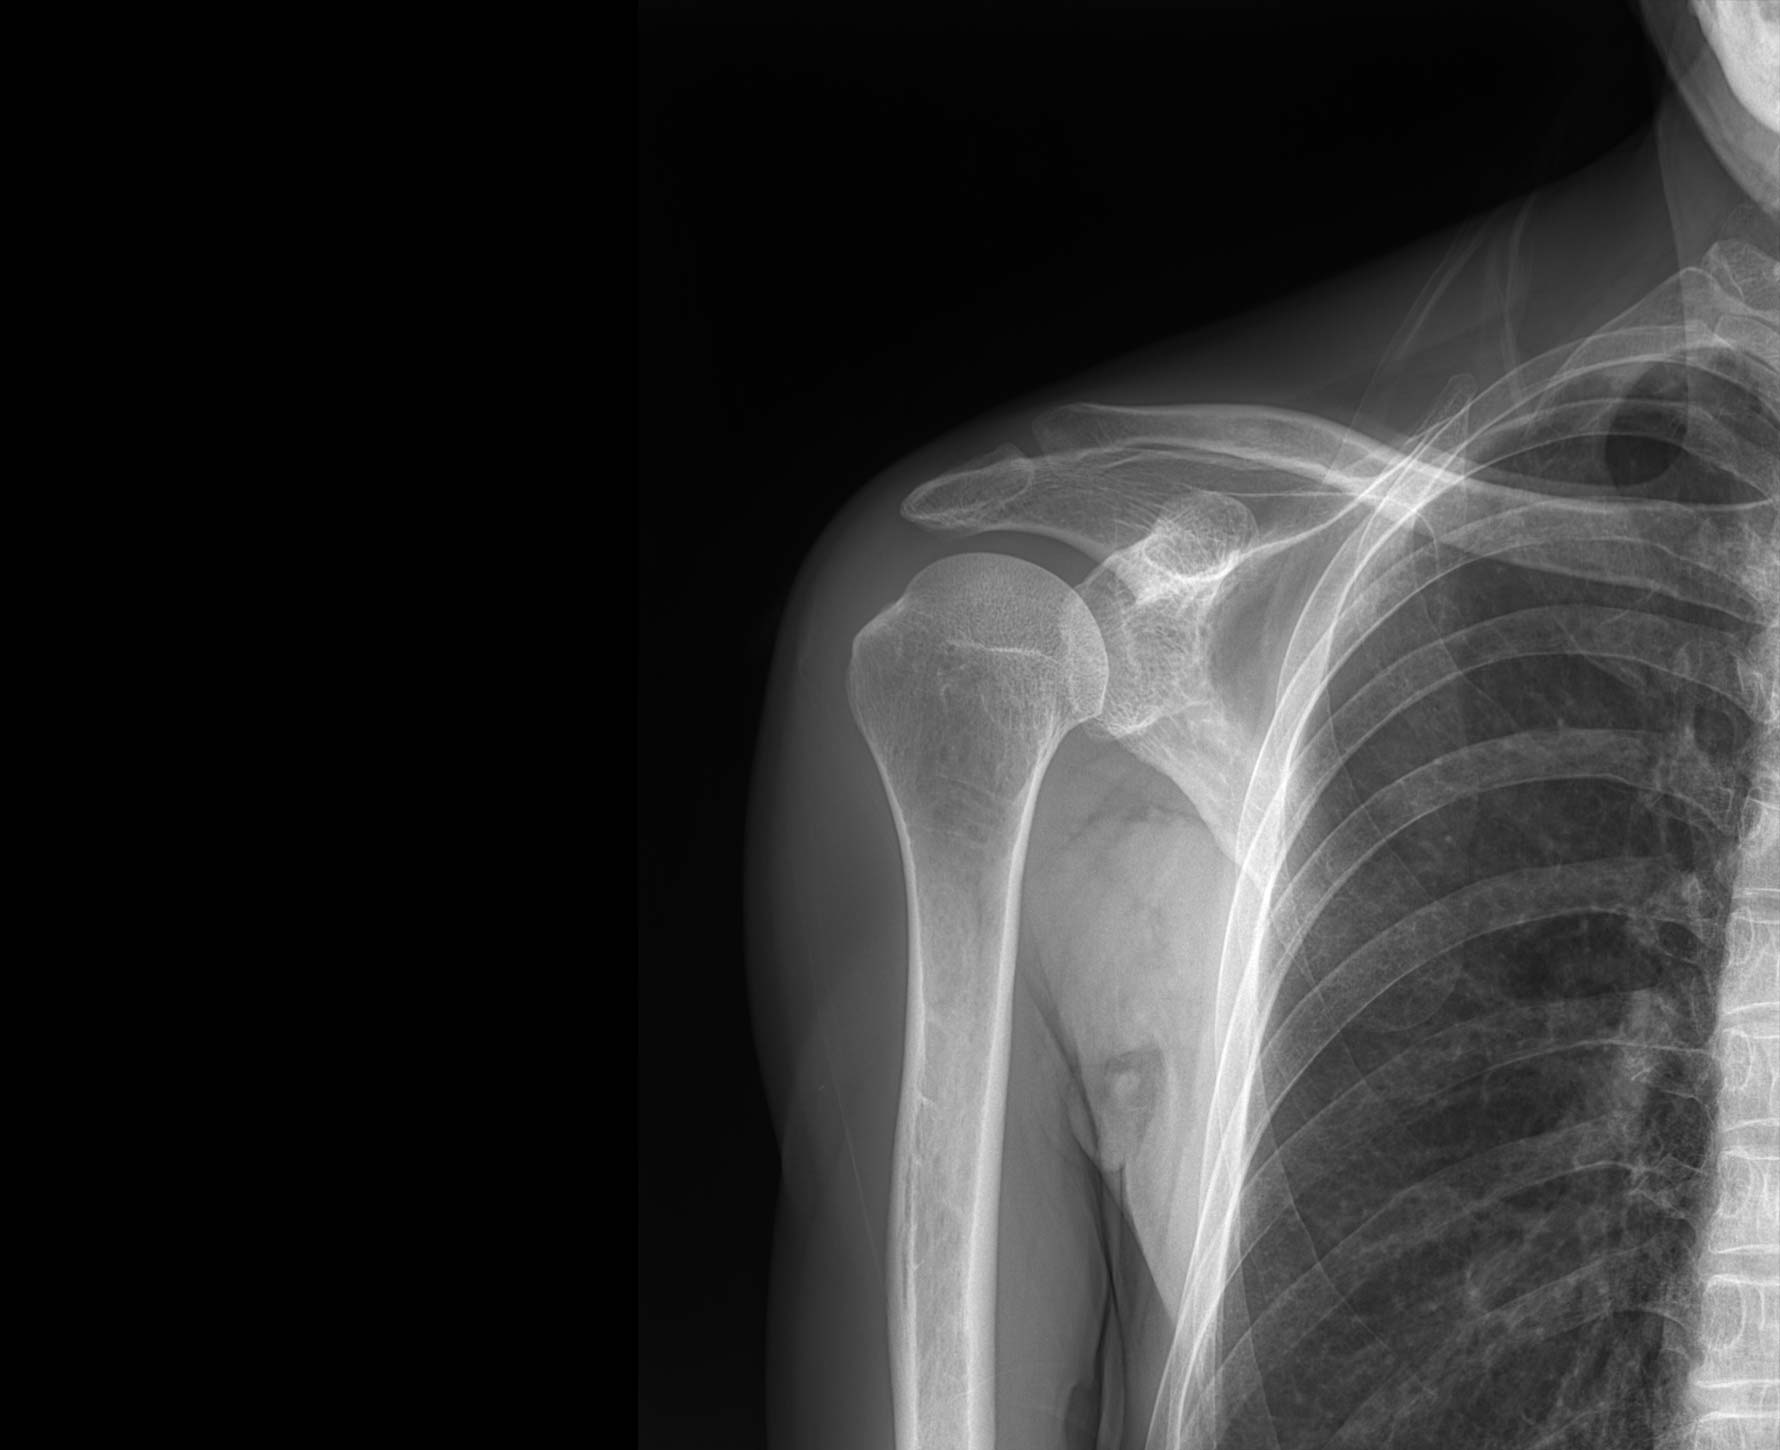

適用于全身各

部位透視檢查